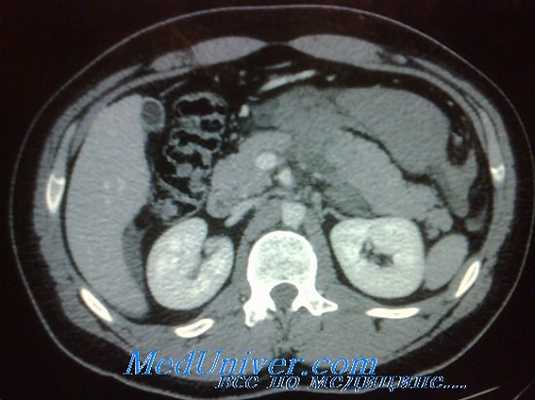

КТ – диагностика повреждений паренхиматозных органов, аорты, очагов кровоизлияний в брюшной полости и забрюшинном пространстве. Использование рентгеноконтрастных веществ (в/в или внутрь) расширяет возможности КТ и позволяет одновременно визуализировать паренхиматозные и полые органы брюшной полости. Повреждения почек и забрюшинные гематомы выявляют с помощью КТ живота, которую нужно провести каждому больному с гематурией и стабильной гемодинамикой (Уровень рекомендации - C)[3]. Необходимость проведения ИВЛ пациенту не является противопоказанием к КТ. Противопоказание - нестабильная гемодинамика пациента. Когда имеется подозрение на повреждение печени/селезенки КТ позволяет исключить повреждения требующие экстренного оперативного вмешательства (Уровень рекомендации - В) [3]. КТ рекомендуется у гемодинамически стабильных пациентов с неоднозначными данными физикального осмотра, сочетанной неврологической травме или множественной экстраабдоминальной травме. При негативном результате КТ пациент госпитализируется для динамического наблюдения (уровень доказательства – I) [5]. КТ позволяет выбрать консервативную тактику ведения у пациентов с солидным характером повреждения внутренних органов (уровень доказательства – I) [5]. У гемодинамически стабильных пациентов ДПЛ и КТ являются дополняющими друг друга методами диагностики (уровень доказательства – I) [5]. КТ не может использоваться как единственный метод диагностики для исключения повреждений кишки, диафрагмы, поджелудочной железы (Уровень рекомендации - В) [3]. КТ БП достоверно идентифицирует гемоперитонеум у пациентов с ТТЖ (Уровень рекомендации - В)[3]. Пероральное введение контраста при КТне является обязательным при диагностике ТТЖ (Уровень рекомендации - В) [3].